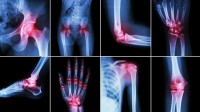

Artritídy kĺbov sú zápalové kĺbové ochorenia rôzneho pôvodu s výraznou imunitnou zložkou (reumatoidná artritída), ale tiež artritídy pri ďalších ochoreniach ako dna, lupienka a pod.

K najčastejším artritidám postihujúcich kĺby patrí reumatoidná artritída, Bechterevova choroba a psoriatická artritída. Presná príčina choroby nie je známa, ale hlavným škodlivým mechanizmom je neinfekčný chronický vnútrokĺbový zápal – autoimunitný proces, keď imunitný systém napáda a ničí vlastné tkanivá. Prejavuje sa ako opuch, horúčava, citlivosť na dotyk, bolestivosť a znížená funkčnosť. Zápal po nejakej dobe vyústi v deštrukciu a deformáciu kĺbu.

Ochorenie sa prejavuje bolestivosťou, pocitom rannej stuhnutosti, opuchom drobných kĺbov rúk, príp. i kĺbov iných. Najčastejšie sú zápalovo postihnuté drobné kĺby ruky, zápästia a členkový kĺb, ale aj bedrá a kolená.